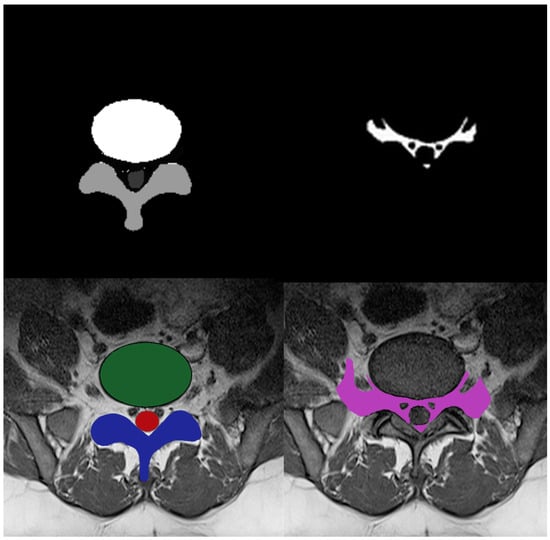

The initial step in using deep learning models is to prepare the training data for the classifiers. The deep learning approach is tremendously data-hungry because it also incorporates representation learning [33]. Multi-ROI and single-ROI training datasets were employed in our experiment. The first mask shown in Figure 3, contained IVD, PE, and TS, but the second mask only included the AAP region, so stenosis diagnosis could be performed after measuring this region.

Figure 3.

Four-class manual segmentation mask.